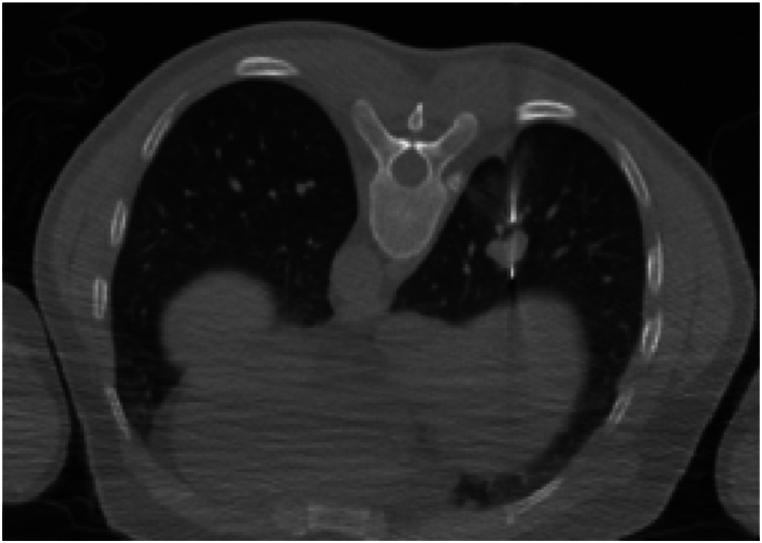

Primary malignant melanoma of lung (PMML) are relatively rare, accounting for about 0.4 % of all malignant melanomas and only 0.01 % of all lung tumors, and PMML with distant metastases found at diagnosis is extremely rare. A case of PMML presented as multiple solid and ground glass pulmonary nodules with brain, liver,intrapulmonary and lymph nodes metastasis was reported in this study. A 42-year-old man had a headache for 10 days after symptomatic treatment in the department of neurology in our hospital, but the above symptoms did not improved. Multiple nodules were considered by head MRI. Chest CT showed two solid nodules in the upper and lower lobes of the right lung and multiple ground glass nodules in both lungs. To further clarify the diagnosis,CT-guided percutaneous puncture biopsy of pulmonary nodule was performed. The pathology revealed malignant melanoma of .NRAS + BRAF gene test, showing BRAF gene exon 15 V600E mutation Dalafenib and trametinib were given targeted therapy after discharge. After 1 month follow-up, all lesions were significantly decreased. PMML presenting as solid and ground glass pulmonary nodules with multiple metastases is extremely rare. The early identification of pathological biopsy and genetic testing is crucial for precise treatment and enhancing prognosis.

原发性肺恶性黑色素瘤(PMML)相对罕见,约占所有恶性黑色素瘤的0.4%,仅占所有肺肿瘤的0.01%,而诊断时发现有远处转移的PMML极为罕见。本研究报告了1例表现为多个实性和磨玻璃样肺结节并伴有脑、肝、肺内及淋巴结转移的PMML病例。一名42岁男性在我院神经内科对症治疗后头痛10天,但上述症状未改善。头颅MRI检查考虑为多发结节。胸部CT显示右肺上叶和下叶有两个实性结节,双肺有多个磨玻璃结节。为进一步明确诊断,对肺结节进行了CT引导下经皮穿刺活检。病理显示为肺恶性黑色素瘤。NRAS + BRAF基因检测显示BRAF基因第15外显子V600E突变,出院后给予达拉非尼和曲美替尼靶向治疗。随访1个月后,所有病灶均明显缩小。表现为实性和磨玻璃样肺结节并伴有多发转移的PMML极为罕见。早期进行病理活检和基因检测对于精准治疗和改善预后至关重要。